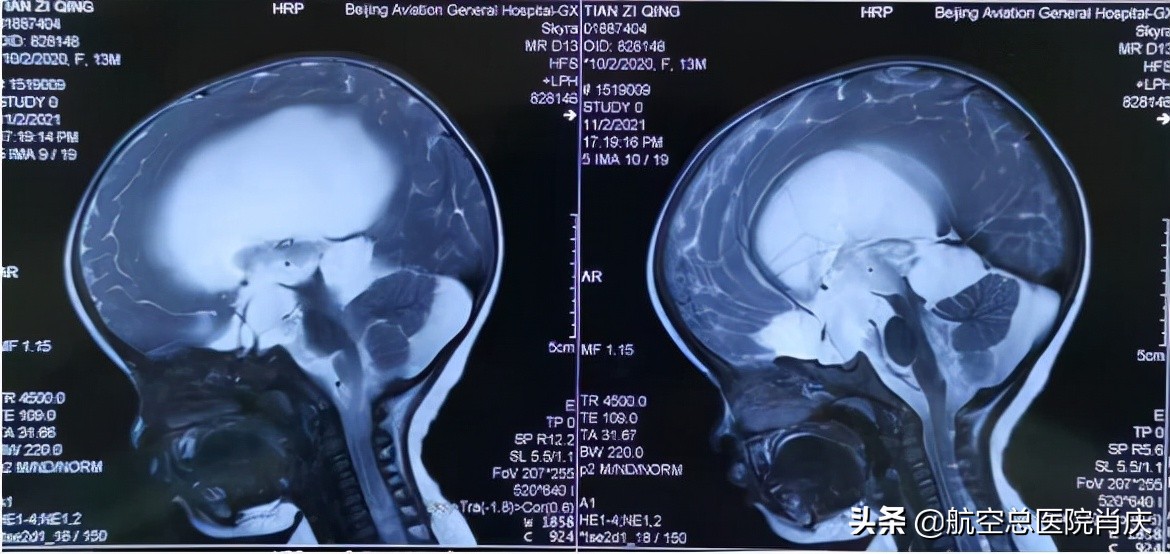

(术前矢状位片示三脑室底膨隆,脑室扩张,四叠体池囊肿)

(术前冠状位片示脑室扩张,双侧颞极蛛网膜囊肿)